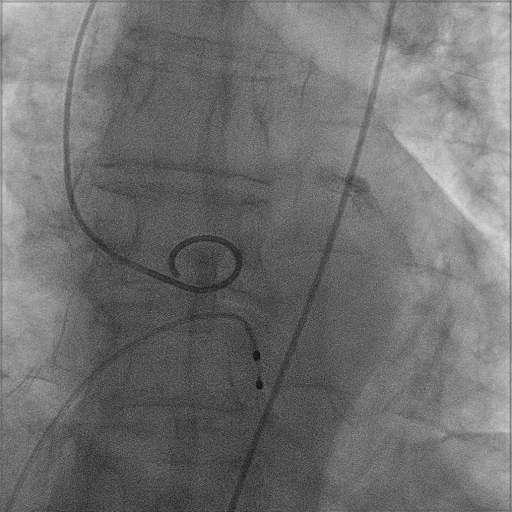

主动脉根部造影

22mm球囊预扩张

Venus-A L26瓣膜精准定位

22mm球囊后扩张

瓣膜形态良好,结果满意